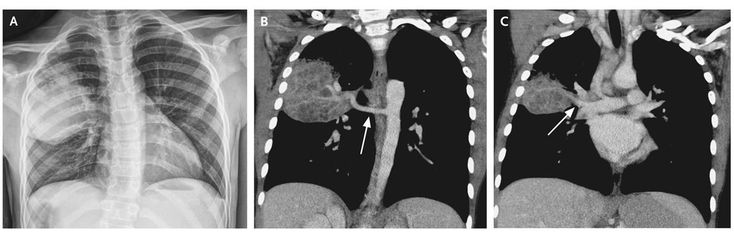

A 9-year-old boy with a history of a lung lesion suspected to be a pulmonary sequestration or a congenital cystic adenomatoid malformation presented to the emergency department with fever and chest pain. A chest radiograph (Panel A) showed a large opacity in the right lung, abutting the minor fissure and displacing it downward. Computed tomography of the chest revealed a large heterogeneous mass with scattered areas of low attenuation, suggesting mucous impaction, and a single large systemic artery (Panel B, arrow) providing vascular supply from the descending aorta. No air bronchograms were evident within the mass. A vein arising from the posterior portion of the mass drained into the right superior pulmonary vein (Panel C, arrow). The patient underwent a right upper lobectomy. Pulmonary sequestration is a congenital disorder characterized by anomalous lung tissue that lacks normal communication with the tracheobronchial tree, which increases the likelihood of infection. The patient recovered without complications and since the operation has had no further pulmonary problems.